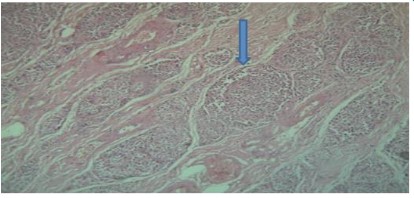

The third specimen received was omental tissue, measured 7 x 3 x 2 cms and was fibrofatty. On microscopy from multiple sections showed presence of nesting pattern with medium sized polygonal cells contain eosinophilic cytoplasm, round to oval nuclei and finely granular salt pepper chromatin. No necrosis found. Immunohistochemistry was performed.

Figure 11: Neuroendocrine deposits in omentum fat, 100x

Immunohistochemistry showed pancytokeratin positive, chromogranin positive, synaptophysin positive, CD 56 weakly positive, Leucocyte common antigen- negative with Ki-67 less than 1%. The diagnosis was suggestive of well differentiated neuroendocrine tumour.